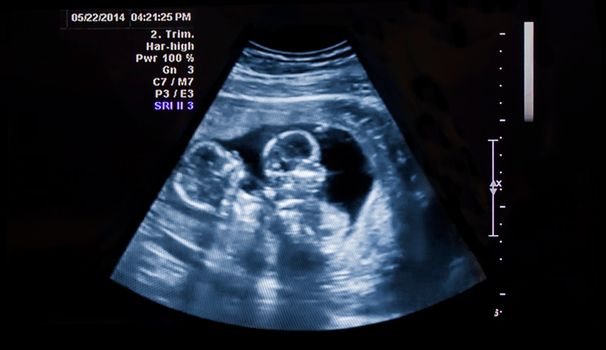

Doctors have confirmed that a pair of twins born in Vietnam have different fathers, effectively making them half-siblings.

The children’s parents initially became suspicious when their extended family pointed out that one of the twins (now two years old) grew thick curls while the other had thin, straight hair.

Now scientists at the Center for Genetic Analysis and Technologies in Hanoi, have confirmed the twins are bi-paternal; they have the same mother but different fathers.

Bi-paternal twins are extremely rare and occur when a woman releases two eggs (which can stay viable for 24 hours after ovulation). Because sperm can potentially survive up to five days inside a woman’s body, it stands to reason that a woman could get pregnant twice during that time.